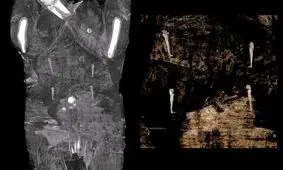

دانشمندان لهستانی که اخیرا موفق به شناسایی نخستین جسد مومیایی شده زن باردار مصری شدهبودند، با این سوال مواجه شدند که…